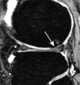

Amnion rupture sequence with exencephaly